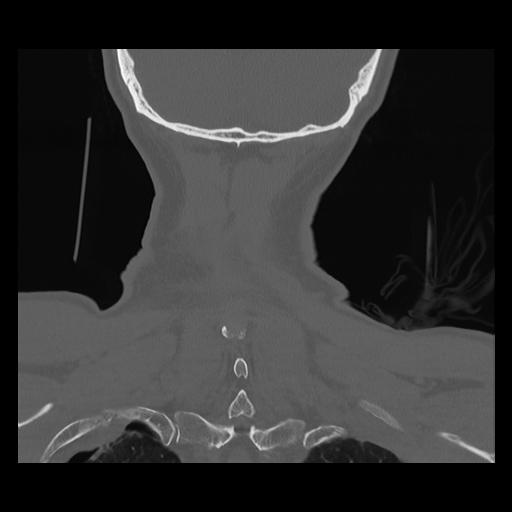

16 HUESO,,Coronal,2.000,HUESO,Coronal,